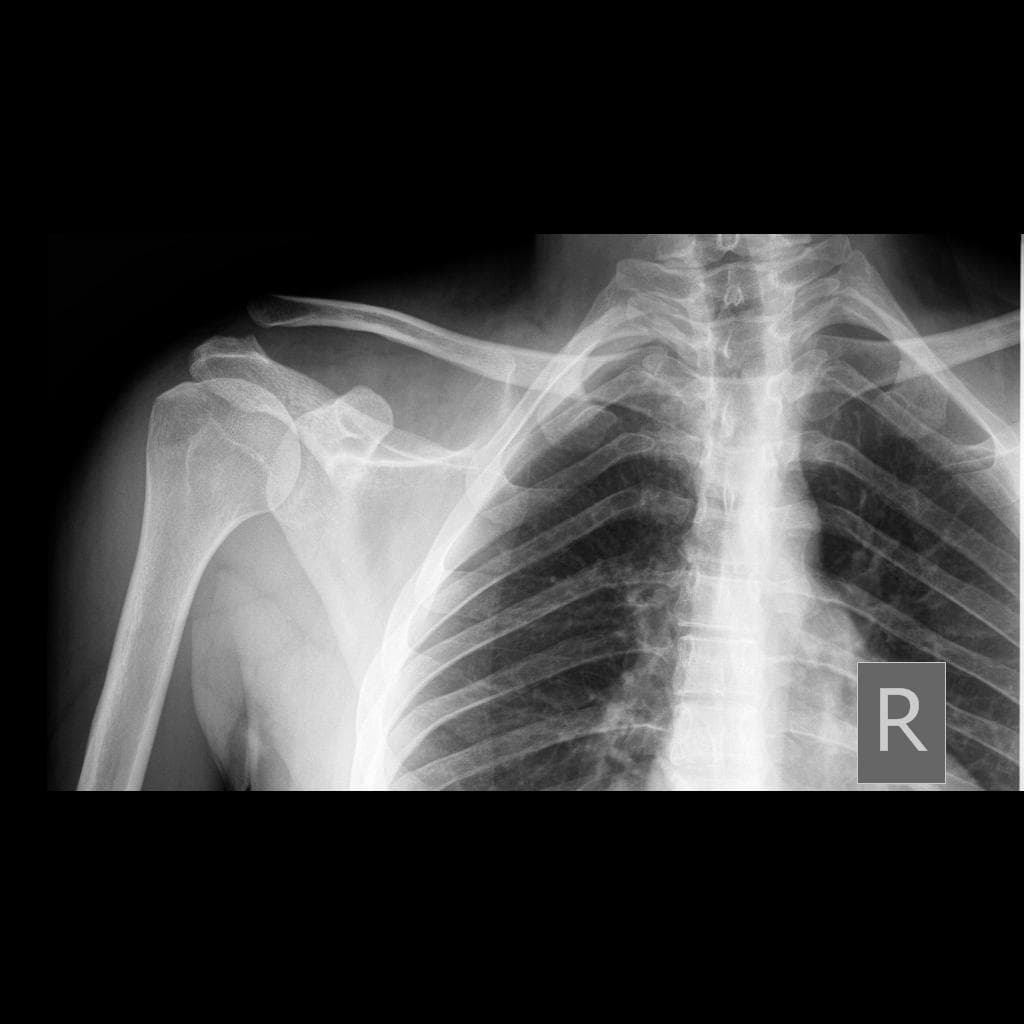

Viêm khớp nhiễm trùng – khớp cùng đòn mỏm cùng (septic arthritis - acromioclavicular joint)

Đau khớp vai phải, sốt

- Có các ổ dịch ngấm thuốc viền (peripherally enhancing collections) xung quanh khớp cùng đòn mỏm cùng phải.

- Các ổ này đi kèm với tín hiệu bất thường ở tủy xương trong mỏm cùng (acromion) và đầu xương đòn (distal clavicle), cùng với các ổ ăn mòn vỏ xương (cortical erosions) ở xương đòn.

- Ngoài ra, thấy nhiều ổ dịch ngấm thuốc viền kích thước khác nhau nằm trong mô dưới da và các mặt phẳng cơ.

- Các ổ này lan vào các cơ thang (trapezius), cơ delta (deltoid) và cơ ngực lớn (pectoralis), đi kèm tín hiệu bất thường và ngấm thuốc thì tĩnh mạch cửa (post-contrast enhancement) ở các cơ lân cận và mô dưới da phía trên.

- Các cắt ngang ngực cho thấy các đám mờ dạng nốt (nodular opacities) ở phổi phải.

- Thấy một mấu xương nhỏ mọc ra ở bờ trong xương vai, có lớp sụn che phủ dày khoảng 4,5 mm.

- Viêm khớp nhiễm trùng (septic arthritis) tại khớp cùng đòn mỏm cùng là tình trạng hiếm gặp, thường xảy ra do lan truyền theo đường máu, chấn thương hoặc do nhiễm trùng lan trực tiếp từ vùng lân cận.

- Chụp cộng hưởng từ (MRI) là phương tiện ưu tiên để chẩn đoán sớm, cho phép đánh giá tràn dịch khớp, ngấm thuốc màng hoạt dịch, tổn thương mô mềm quanh khớp và các thay đổi xương kèm theo.

- Trong trường hợp này, sự hiện diện của các ổ dịch ngấm thuốc viền tập trung quanh khớp cùng đòn mỏm cùng, kết hợp với bất thường tín hiệu tủy xương và các ổ ăn mòn vỏ xương ở xương đòn và mỏm cùng, hỗ trợ chẩn đoán viêm khớp nhiễm trùng. Viêm tủy xương kèm theo (osteomyelitis) cũng là một khả năng rất cao.

- Các ổ dịch lan rộng trong cơ và dưới da, ảnh hưởng đến các cơ thang, cơ delta và cơ ngực lớn, biểu hiện cho sự lan rộng của nhiễm trùng với sự hình thành nhiều ổ áp xe – đây là một biến chứng đã được ghi nhận trong nhiễm trùng kéo dài hoặc tiến triển nhanh.

- Các đám mờ dạng nốt (nodular opacities) thấy trên phổi phải có thể là các huyết khối nhiễm khuẩn (septic emboli) hoặc một quá trình nhiễm trùng liên quan như lao phổi hoạt động, cần được đánh giá thêm bằng lâm sàng và hình ảnh học.

- Mấu xương bất thường ở bờ trong xương vai, có lớp sụn mỏng che phủ, phù hợp với u sụn xương (osteochondroma) – phát hiện tình cờ.

- Đã thực hiện dẫn lưu ổ dịch dưới hướng dẫn hình ảnh, thu được khoảng 400 mL dịch mủ, xác nhận bản chất nhiễm trùng của tổn thương.